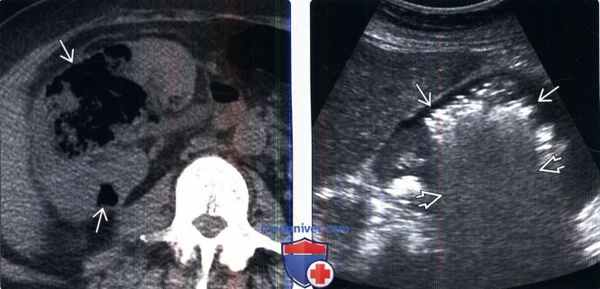

(Слева) КТ без контрастирования, аксиальная проекция: большое скопление газа В в правой почке. Этот признак характерен для эмфизематозного пиелонефрита. Скопления жидкости нет. КТ-метод выбора для постановки диагноза и оценки распространения газа.

(Справа) УЗИ правой почки в сагиттальной плоскости: у этого же пациента визуализируются эхо-сигналы в паренхиме почки, ассоциированные с «грубой акустической тенью».